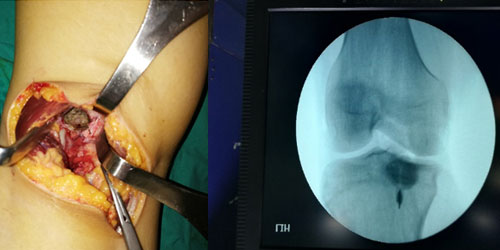

CHONDROBLASTOMA-CODMAN’S TUMOR

Chondroblastonm is a rare benign bone tumor of cartilage origin. Also known as Codman’s tumor. The most common age of chondroblastoma is between 10-30 years and it is more common in males (3/2).